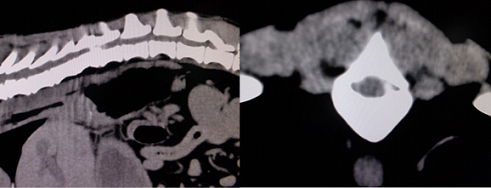

【画像診断】~ダックスフンド、雄10歳、グレート3の椎間板ヘルニア~

▲同じく胸椎T11-12、3D画像のCT像、ワークステーションを用いたCTの仮想内視鏡像